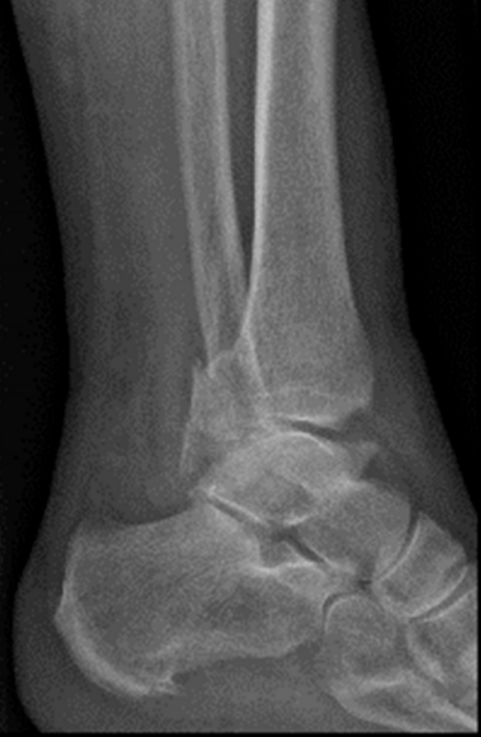

患者为83岁女性,于光滑平面滑倒后致三踝骨折,后踝为Bartonček 2型骨折,累及后外侧骨块及腓骨切迹(图2a–d)。相关合并症包括:骨量减少、软组织条件不良(皮肤呈羊皮纸样改变)、2型糖尿病(HbA1c 7.7%)。

image.png

(a)

(b)

(c)

(d)

图 2. (a–d):三踝骨折:(a) 前后位及 (b) 侧位X线片;(c) 轴位及 (d) 矢状位CT图像显示2型后踝骨折伴小中间骨块。